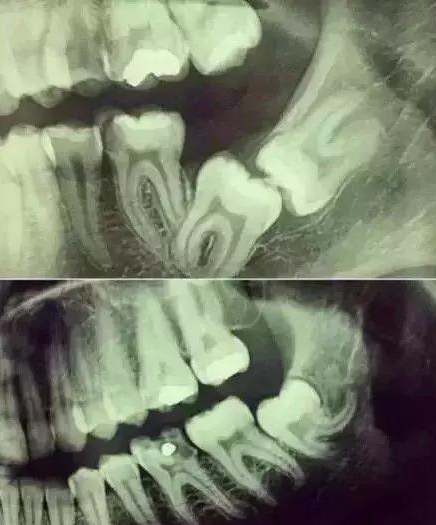

不拍牙片,你永远不知道牙齿能长得多么“奇葩”。

我们的牙齿情况远比我们想象的复杂,肉眼是无法看清全貌的。你敢让医生不拍片就拔,医生还不敢呢。

牙齿本身:生长方向,牙根数目,牙根是否弯曲,膨大等。

与重要解剖结构的位置关系:如上颌磨牙与上颌窦的关系;下颌磨牙与下颌神经管的关系;儿童在混合牙列期恒牙与乳牙胚的关系等。可以减少拔牙的风险。预知其他病变:如颌骨内有无埋伏牙,多生牙,囊肿等。